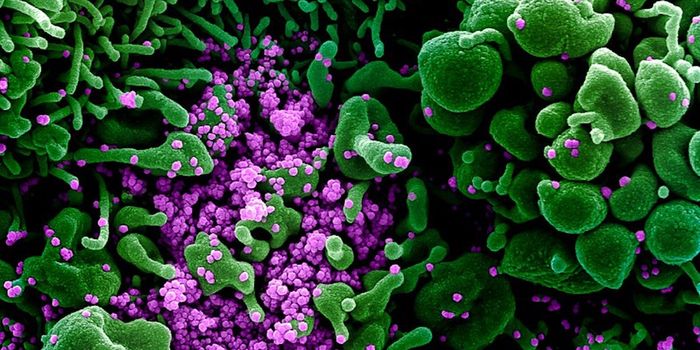

DEC 24, 2020MicrobiologyThe UK recently reported that it had detected a new variant of the SARS-CoV-2 pandemic virus, which causes COVID-19. Thi ...